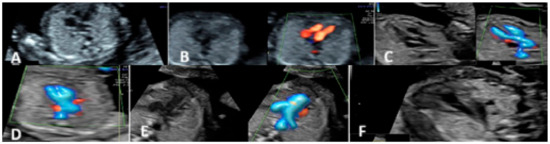

2.1. First Trimester Scanning and Sections

2.2. Second Trimester Scanning and Sections